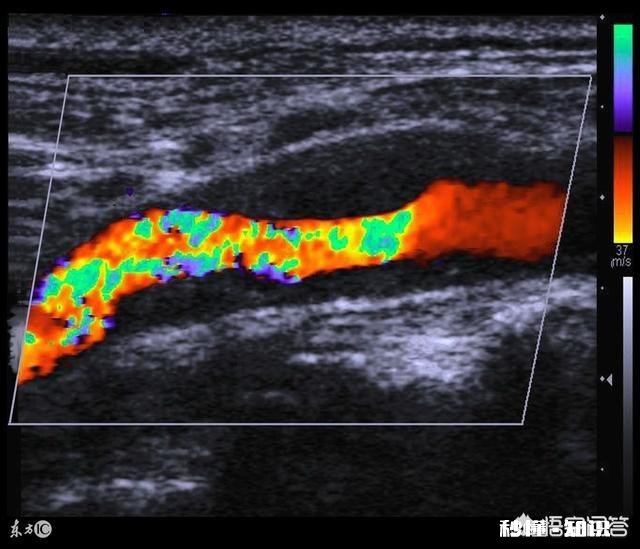

这个标准过于复杂,临床上可以根据超声结果的描述,初步判定是否为易损斑块 。颈超根据斑块内部的回声特点,将斑块分为均匀低回声、中回声、高回声和不均质回声几种,其中易损斑块主要以低均质性回声为主 , 而无症状性斑块以高回声、不均质回声为主 。所以如果颈超结果对斑块的描述为低均质性回声,通常为易损斑块,需要吃降脂药;如果是报的是强回声、高回声斑块,一般已经钙化,不太容易脱落 。

最常用的是颈动脉超声,颈动脉超声根据斑块内部的回声特点 。将斑块分为均匀低回声、中回声、高回声和不均质回声几种类型,易损斑块以低均质性回声为主,而无症状性斑块以高回声、不均质回声为主 。